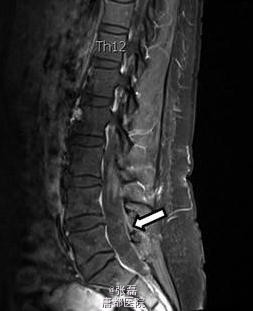

患者女性,46 岁,因头疼加重 2 周住院。住院时表现为颈部僵硬,伴有眩晕。头颅 MRI 未见明显异常。脑脊液结果示:中性粒细胞 133 个 /μl,嗜酸性粒细胞 38%。血清囊虫抗体滴度 106(正常≤0)。 脊髓 MRI 示:颈部单发囊性占位,腰部蛛网膜下腔多发囊性占位。故诊断为脊髓囊虫病,给予阿苯达唑 (2×400 mg/ 天) 驱虫、激素(强的松 60 mg/ 天)抗炎治疗 4 周。治疗期间,患者症状明显缓解,但是在随访 6 个月时,颈部疼痛仍未见缓解,MRI 示颈部囊性占位体积有所增大。